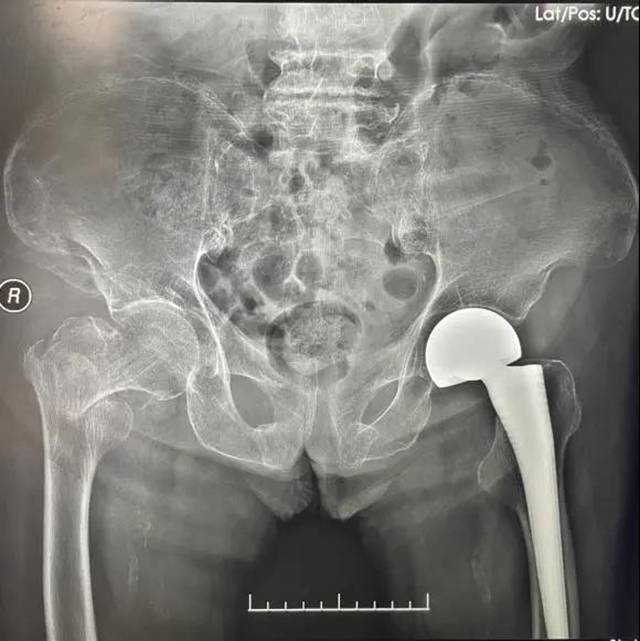

第二次手术,术前X片检查

第二次手术,术后X片检查